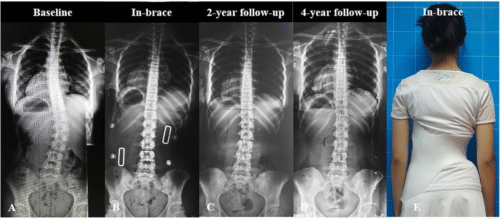

تشير الدراسات الطبية إلى أن الأطفال في سن 11 إلى 15 عامًا هم الأكثر عرضة لخطورة تطور الانحناء. والسبب هو أن هذه المرحلة تمثل فترة البلوغ والنمو السريع، حيث يزداد طول الطفل بشكل ملحوظ خلال وقت قصير.

التدخل المبكر بالعلاج مثل الأحزمة الحديثة PioBrace يمكن أن يوقف أو يصحح الانحناء.

عند الأطفال والمراهقين: الخطر الأكبر هو سرعة تطور الانحناء مع النمو. فمثلاً، إذا تجاوز الانحناء 30 درجة قبل سن 10 سنوات، فإن احتمالية التفاقم تصل إلى 100% إذا لم يتم التدخل. هذا قد يؤدي في النهاية إلى الحاجة لجراحة أو ظهور تشوهات واضحة.

العلاجات غير الجراحية مثل الأحزمة الحديثة PioBrace أثبتت فعاليتها الكبيرة في هذا العمر.

متى يحتاج الطفل المصاب باعوجاج العمود الفقري إلى علاج؟

إذا كان الانحناء بسيطًا، قد يكتفي الطبيب بالمتابعة الدورية.

إذا كان الانحناء متوسطًا، قد يوصى باستخدام الحزام الطبي PioBrace الذي يساعد في تصحيح الانحناء ومنع تطوره.

في الحالات الشديدة التي لا تستجيب للعلاج غير الجراحي، قد يتم اللجوء إلى الجراحة.